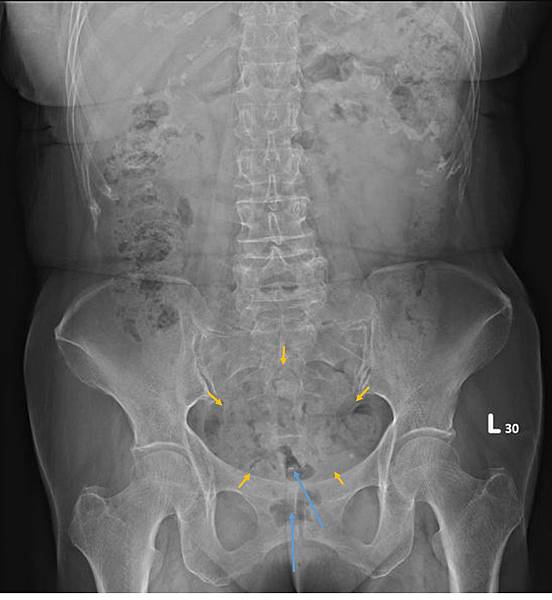

72歲女性,乙狀結腸(黃箭頭)充滿糞便,但她會告訴你,她每天都有解便。如上圖所示,這樣的病例,病人直腸(藍箭頭)糞便清得很乾淨。